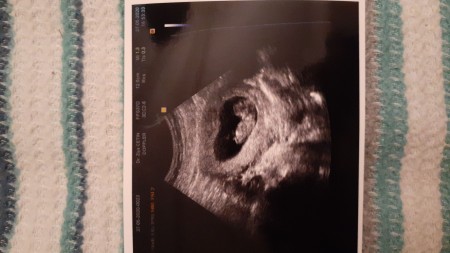

10 Haftalik Gebelik Hamilelik Goruntusu